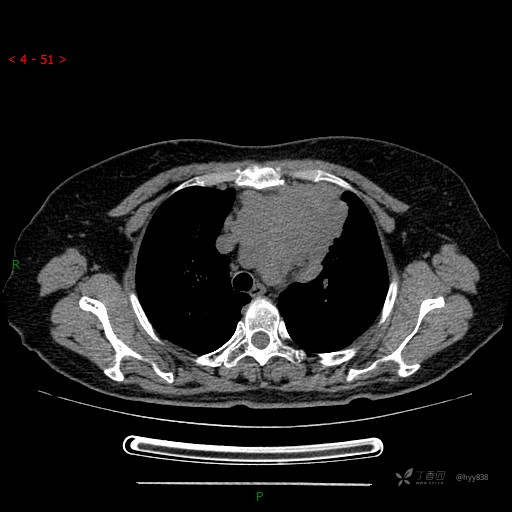

简要病史:患者诉3月余前患新冠肺炎,出现持续性胸闷,活动后可缓解,无胸前区压榨感,无畏寒发热不适,无胸痛咯血、呼吸困难,无恶心、呕吐,无腹痛、腹胀、腹泻等不适,未予以重视,未行特殊处理。患者胸闷持续存在,为进一步诊治,3天前于本院查胸部CT提示前纵膈团块状软组织密度影,肿瘤性病变可能,心包积液,左上肺磨玻璃结节,右下肺增殖灶可能建议进一步检查。门诊以“前纵膈占位” 收入我科。 患者本次起病来精神、食欲、睡眠尚可,大小便正常,体力、体重无明显变化。

辅助检查:CT

临床诊断:纵隔占位

动脉期